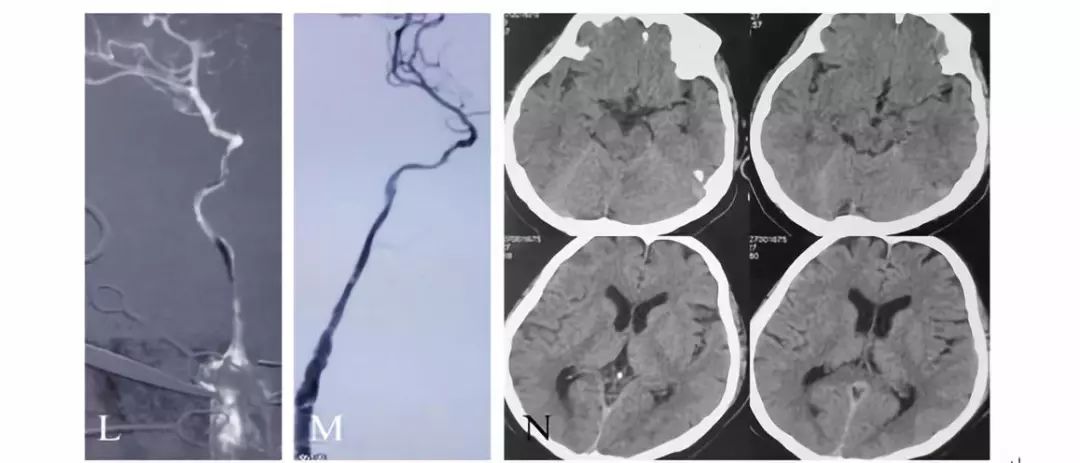

全麻下,血管造影显示右侧颈内动脉起始段完全闭塞,同侧眼动脉逆行充盈右侧颈内动脉,向近端反流到海绵窦上段同3月前的造影

先行颈动脉近端闭塞处切开并行内膜剥脱,再切口处置入动脉鞘后,用300cm 0.014微导丝交换出微导管用1.5mm×20mm gateway 行闭塞段扩张,造影显示右侧颈动脉闭塞段通畅

再使用3mm×20mm球囊行从上往下预扩张C2段三次,扩张后置入ENTERPRISE 支架4.5mm×28mm自膨支架两枚,经股动脉造影显示颈动脉全程完全畅通。复查CT未见新发梗死灶。